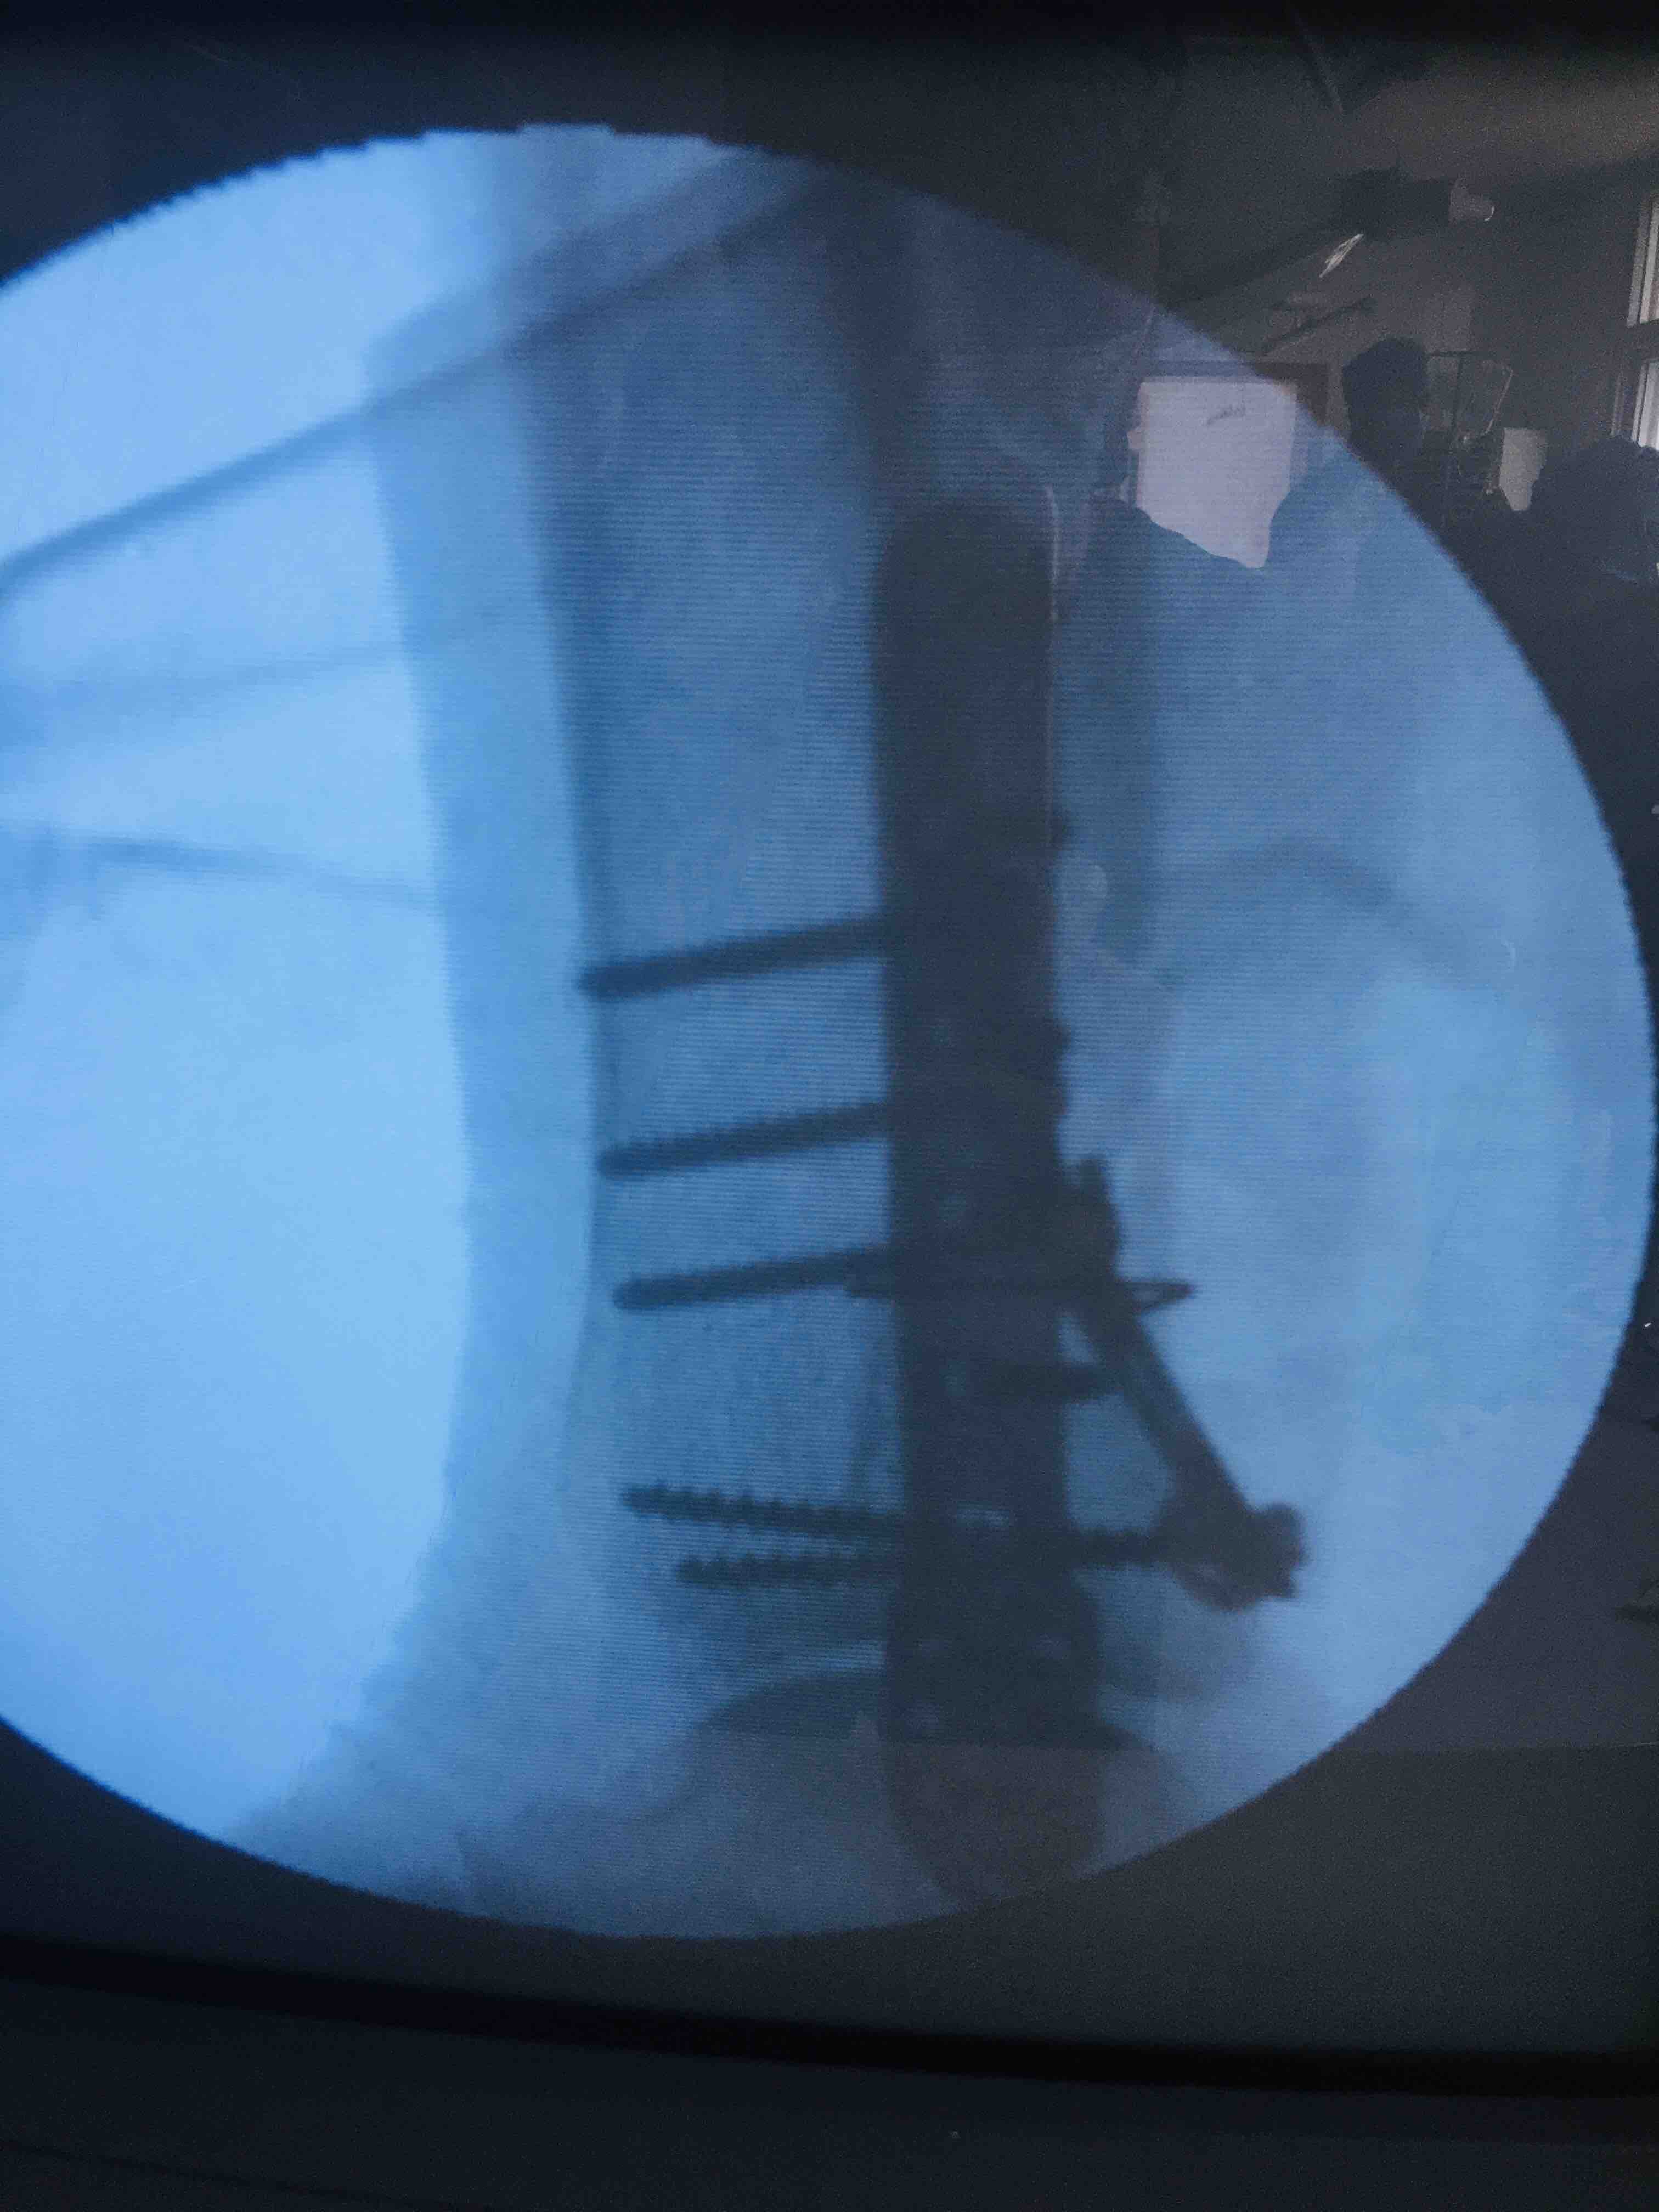

三踝粉碎性骨折(切复内固定术)

摔伤后左踝肿胀,疼痛,活动受限1小时入院。既往身体状况一般。无特殊不良癖好。

生命体征平稳,心肺复未见异常。左踝肿胀明显,畸形,局部皮色发红,皮温高,压痛及纵向叩击痛阳性,末梢血运感觉正常。

急诊行骨牵引,消肿等处理,在腰麻下行切复内固定术,术后抗炎,消肿。